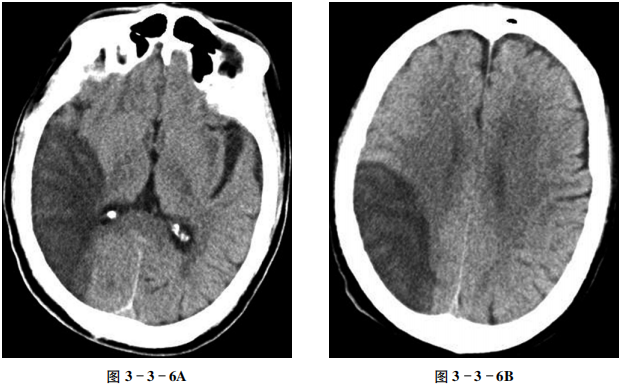

大脑半球脑梗死

【病史摘要】

男性,69岁。5天前突然肢体乏力、跌倒伴言语不清。

【CT征象】

平扫示右颞、枕、顶叶扇形不均匀低密度区,右侧脑室下角略受压,中线结构未见明显偏移(图3-3-6A、B)。

【重要征象】

大脑前中动脉供血区脑组织低密度,边界不清。

【CT拟诊】

①脑梗死。②脑脓肿。③恶性脑肿瘤。

【最终诊断】

缺血性脑梗死。

【评述】

脑梗死是指因血管阻塞而造成脑组织缺血性坏死。在急性脑血管疾病中,脑梗死占50%~80%。根据脑梗死的原因,通常分为脑血管阻塞和脑部血液循环障碍两大类,前者又可分为血栓形成和栓塞,后者多是在脑血管原有病变的基础上由各种原因造成的脑组织供血不足所致。CT平扫对于急性脑梗死的显示能力有限,大多还是要结合临床症状、CT灌注技术及MRI的DWI序列方可正确判断。

CT表现

①缺血性脑梗死在24小时内,58%的患者可见异常。可出现相应部位脑沟变窄或消失、灰白质分界不清,或轻微占位征象,但通常在发病6小时后方可显示。有时候,采用窄窗显示CT平扫图像,可以增加梗死灶与正常脑组织对比度,有利于病灶检出。少数可见血管腔内高密度影,即“致密的大脑中动脉征”。②在2~15日,梗死的低密度病灶显示最清楚,范围与所累及血管的灰白质的分布相一致,常为楔形。有不同程度的脑水肿和占位征象。脑水肿的出现率为20%~70%,一般在梗死第2周水肿基本消退,少数可见少量出血,好发于灰白质交界处。③脑梗死后2~3周,梗死区密度较前增高,在梗死区内和边缘出现弧形或结节状等密度或稍高密度影,病灶边缘可变得不清楚,较小的病灶可完全为等密度,这种变化称为“模糊效应”;占位效应减轻或消失。④在脑梗死后4~5周,梗死病灶密度接近于脑脊液,但范围较急性期小,这与胶质增生有关;邻近脑沟、脑池及脑室扩大。

鉴别诊断

①恶性脑肿瘤:CT平扫肿瘤实性成分呈稍高密度或高密度,瘤周可伴程度不一的指状水肿,占位效应显著。转移瘤多发生在皮髓质交界区,肿瘤实性部分较水肿密度高,瘤周水肿重。②脑脓肿:脑炎早期时CT平扫呈边缘模糊的低密度区,周边伴指状低密度水肿区,CT增强扫描或MRI-DWI序列有助于鉴别。本例仅使用CT平扫,因此单纯依靠影像鉴别两者相对较难,需要密切结合临床病史,或进一步进行MRI检查。